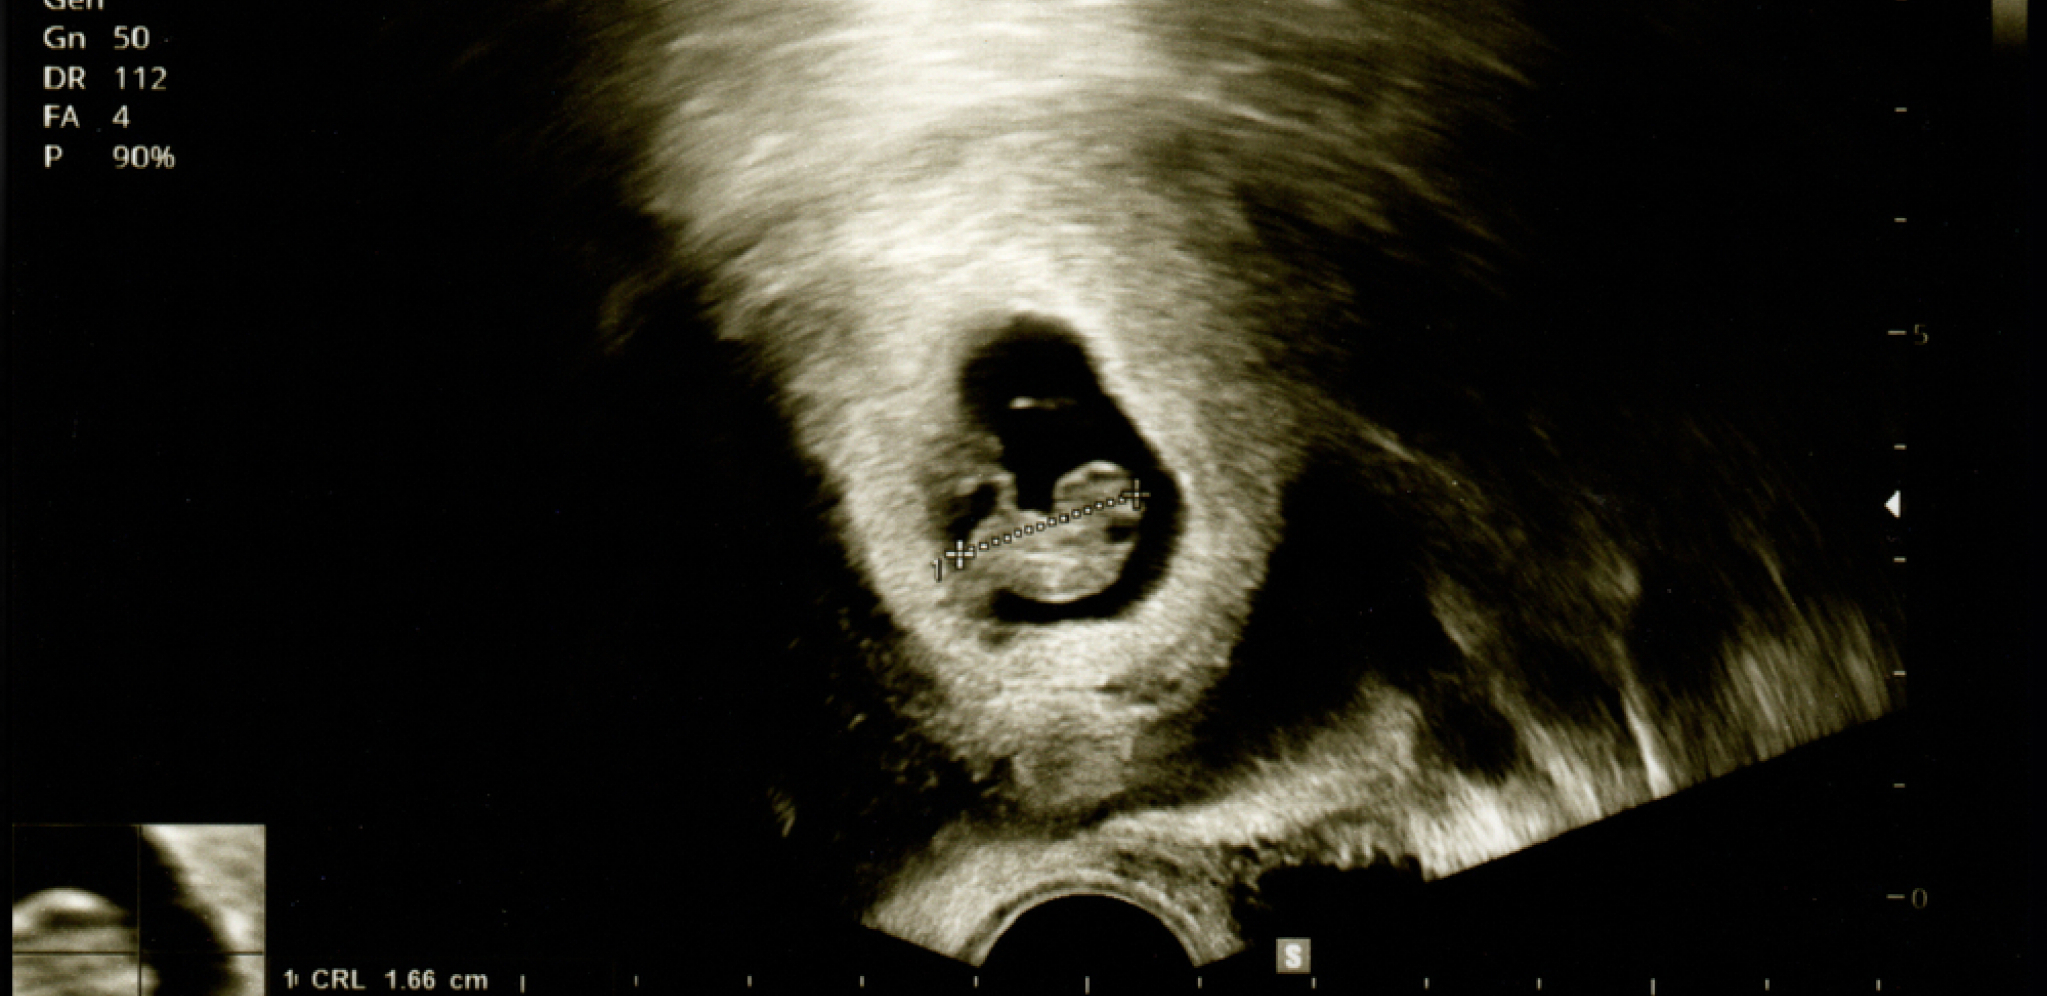

Naime, ona je imala je aferu samo nekoliko dana od njihovog poslednjeg seksa, a ultrazvuk je pokazao da je otac zapravo njen ljubavnik.

- Ultrazvuk daje indikaciju začeća, a time i verovatni datum rođenja izrađen od datuma poslednje menstruacije žene. Ipak, jedini način na koji ćete sa sigurnošću znati ko je otac jeste da uradite DNK test nakon što se dete rodi. Što se tiče vaše veze, ako ste bili srećni pre i nakon ovog privremenog razdvajanja, verovatno možete da učinite da vaša veza funkcioniše. Ali morate da naučite bolje da komunicirate zajedno - odgovorila mu je Didri.